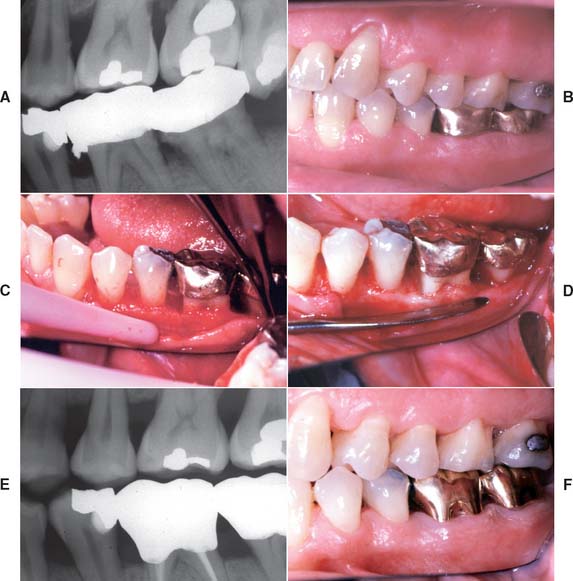

A small number of patients may not have responded well to previous occlusal treatment or may resume parafunctional activity some time after completion of the active phase of fixed prosthodontic treatment. Although resolving the underlying etiology is preferable, a nightguard can occasionally be prescribed (Fig. 32-15). Its design is identical to that of the occlusal device described in Chapter 4 for treating neuromuscular symptoms resulting from malocclusion. However, the device is worn only at night. If the patient primarily clenches, the dentist should consider a slightly flatter anterior ramp than is ordinarily incorporated in the conventional device.